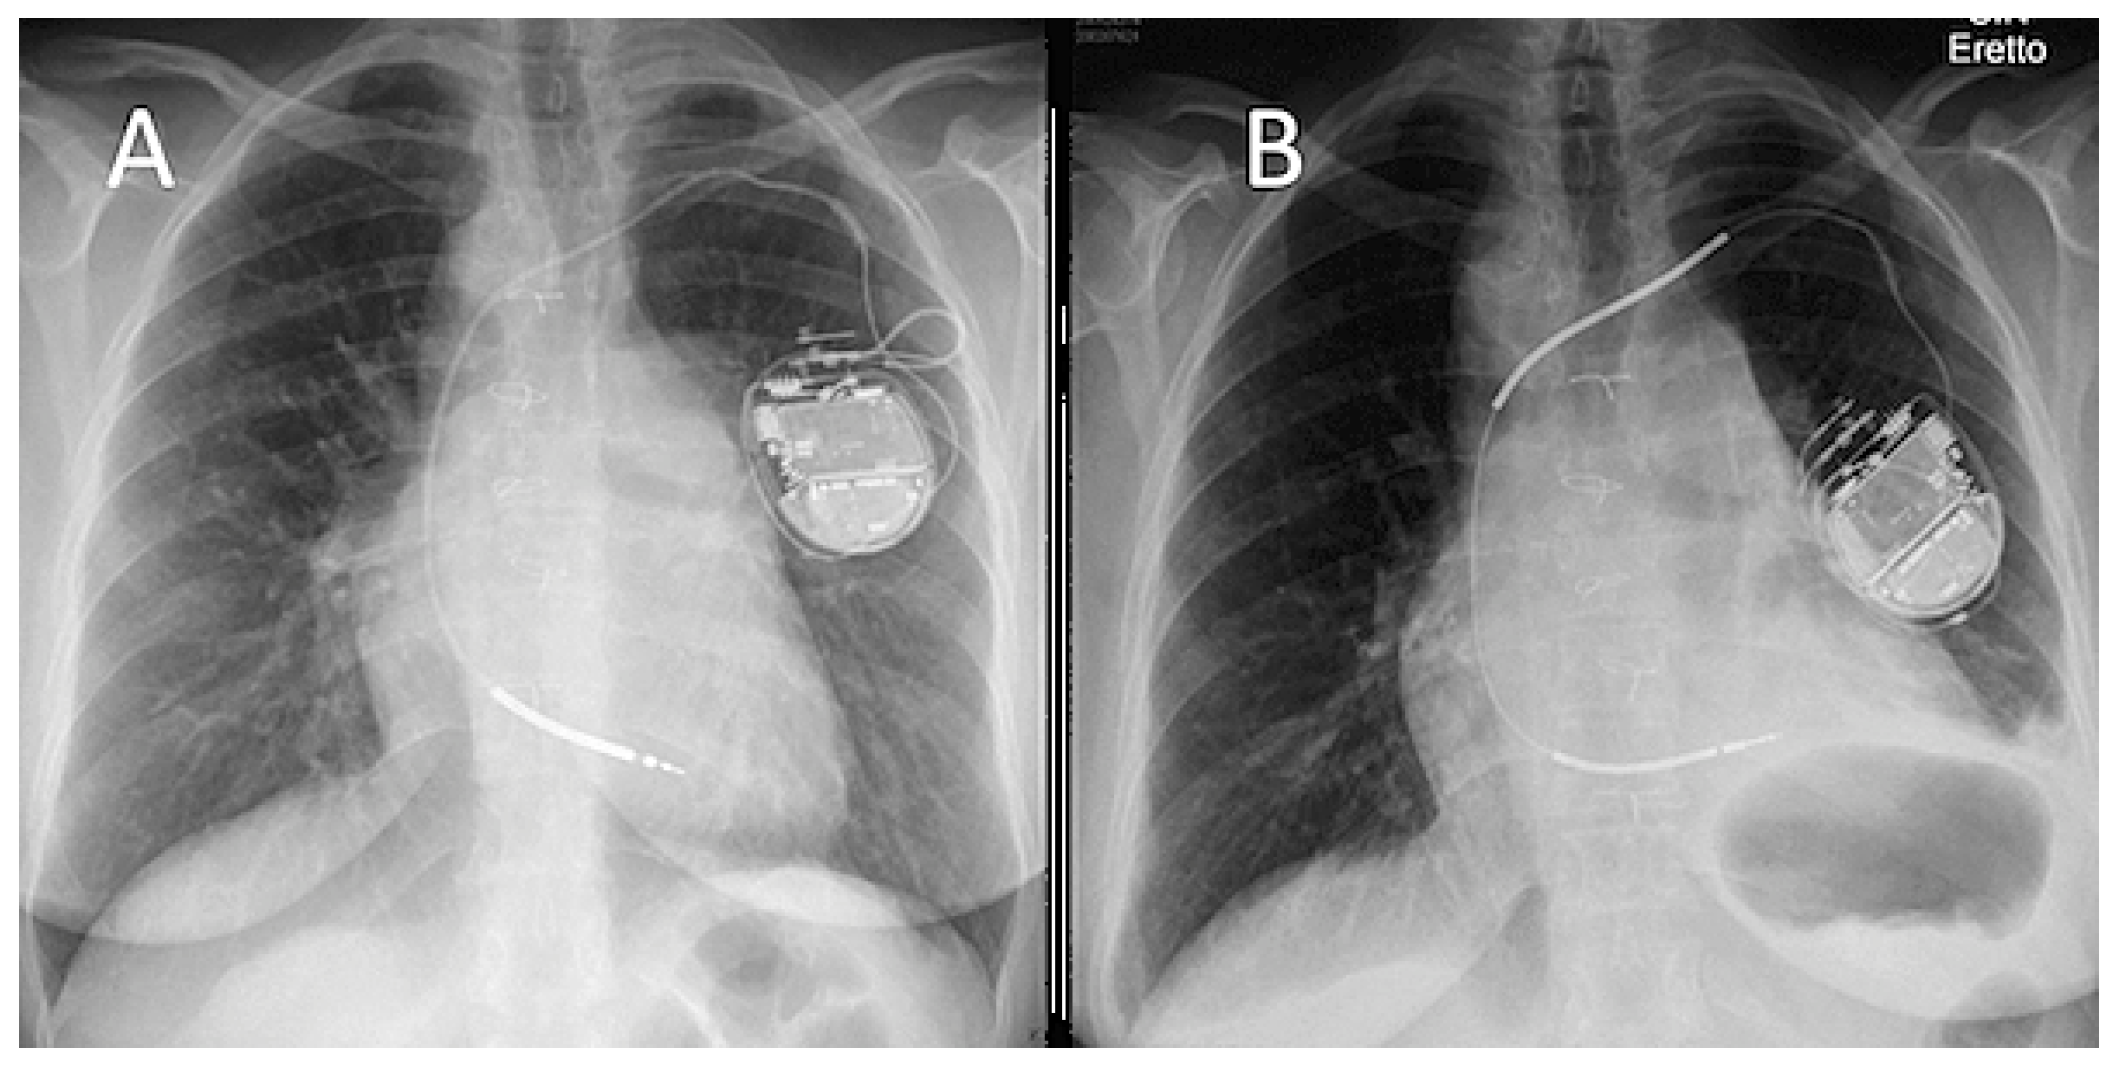

Introduction: Phrenic nerve palsy (PNP) after mechanical transvenous lead-extraction (TLE) was recently described for the first time. We aimed to analyse our TLE database for the presence of PNP.

Methods: All consecutive patients referred to our institution were included in this study. Every available post-procedural chest x-ray was compared to the routinely performed pre-procedural radiographs. A newly elevated hemidiaphragm ipsilateral to TLE was considered indicative of PNP (see figure).

Results: Altogether 255 TLE procedures with extraction of 364 leads were performed. Most common TLE-indication was lead malfunction (63%). Complete radiographic success rate was 97.3% with an In-hospital procedure-related major-complication rate of 2.4%, including one intra-procedural death (0.4%). We identified 5 cases with PNP (2%), all occurring after laser-assisted TLE (see table). Clinical presentation varied from subtle and aspecific chest pain/discomfort to severe and acute dyspnoea, with time to diagnosis varying from immediate to several weeks after the procedure. In 80% of cases, the explanted lead was a defibrillator electrode and the median lead dwelling-time was 70.2 months (29.3; 184.9). In 4 cases the extraction was performed using high-energy laser (pulse-repetition-rate 80 Hz).

Conclusion: To the best of our knowledge, this is the first study reporting the incidence of PNP after laser-assisted TLE. We postulate that the thermal energy generated by laser is not dissipated quickly enough in occluded or heavily calcified lesions, injuring the ipsilateral phrenic nerve at the subclavian level. Our findings advise to carefully consider to increase pulse-repetition-rate at the subclavian level. Larger, possibly prospective studies are needed to evaluate the real incidence through systematic radiological assessment after TLE.

![]() |

| Figure 1. X-ray prior and after transvenous lead extraction showing a newly elevated leftsided hemidaphragm. |